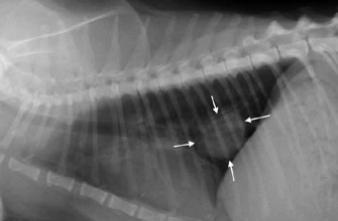

Parmi la cohorte, cinq personnes avaient des cellules cancéreuses circulantes détectées grâce au test, alors même que l’imagerie ne révélait aucune tumeur. Ces personnes ont été suivies régulièrement. Des très petites tumeurs (nodule) ont commencé à se former au bout de deux ans, en moyenne, après le test sanguin (entre 1 an et 4 ans selon les sujets). L’analyse de ces nodules a confirmé le diagnostic d’un cancer du poumon.